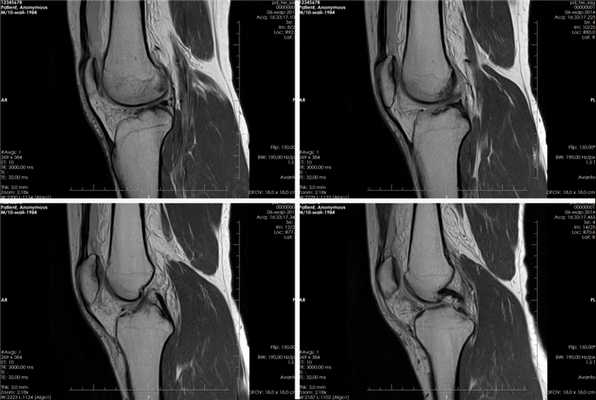

Вывих коленного сустава на МРТ

Вывих коленного сустава - болезненная травма нижней конечности, которая сопровождается повреждением капсульно-связочного аппрата. Вывих коленного сустава также может быть свежим (впервые полученный) или привычным (периодически повторяющийся, часто сочетающийся с полным разрывом передней крестообразной связки).

МРТ коленного сустава проводится в трех взаимно перпендикулярных плоскостях, что делает возможным выявить любые изменения в коленном суставе, например, повреждения внутрисуставного хряща, капсульно-связочного аппарата, менисков, ушиба костного мозга и околосуставных мягких тканей.